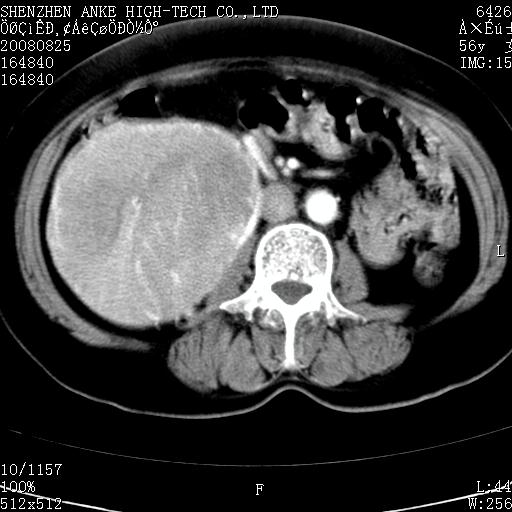

患者,女性,56岁,腰痛3年,查:右腹部约8x10cm肿块,固定,无压痛;8月23日在外院做了平扫,发现右肾巨大肿块(外院具体诊断不祥);今天在我院做了静脉肾盂造影,示:右肾明显增大,分泌功能明显减弱。

1)考虑右肾癌并右肾静脉瘤栓形成。2)脂肪肝。